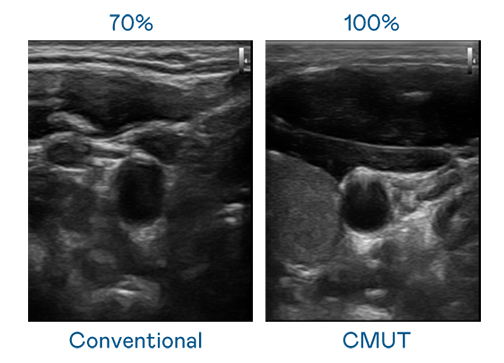

CMUT 技术是一种用电容式微机电元件来产生超音波讯号的技术。与传统 PZT 压电式技术相比,CMUT 频宽增加 30%,更宽频的超音波讯号让影像解析度大幅提升,是实现高影像品质医疗超音波扫描、促进精准医疗发展的关键技术。

大频宽带来超清晰影像

超音波影像的解析度高低,首先取决于探头能发出的讯号频宽。凯发 CMUT 可提供高清晰的超音波讯号,提供高频宽、高灵敏度、影像纹理细节更高的超音波影像,协助医护人员缩短影像判读时间及利用精准的医疗影像进行诊断。